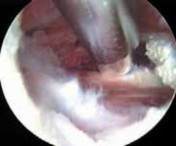

Failure to fully release tendon ■ The iliopsoas tendon forms from the psoas and iliacus muscles. The tendon sometimes

may remain bifid all the way to its insertion on the lesser trochanter. Whether addressing the tendon from the peripheral compartment (

FIG 4A–G

) or from its insertion within the iliopsoas bursa (

FIG 4H,I

), if the tendon looks inordinately small, search for a separate portion of the tendon. Failure to fully release the tendon fibers may result in incomplete resolution of the snapping.

TECHNIQUES A B C D E F G H I ### FIG 4 • A–G. The iliopsoas tendon of the right hip is exposed from the peripheral compartment. A. The initial tendon viewed through a capsular window is fully identified, but is abnormally small. B. This tendon is released with a basket. C. A stump remains. D. This is resected with a shaver. E. Further dissection exposes a more substantial portion of the iliopsoas tendon. F. This is released as well. G. Complete release of the bifid tendon is documented. H,I. Viewing the iliopsoas tendon of a right hip at its insertion on the lesser trochanter within the iliopsoas bursa. H. A bifid iliopsoas tendon is identified with medial (

) and lateral () bands separated by a vessel (

two white asterisks

) coursing perpendicular. I. The lateral band (

black asterisks

) has been released with a flexible RF device, revealing the medial band (

white asterisk

) which subsequently is released. (Courtesy of J. W. Thomas Byrd, MD.)**